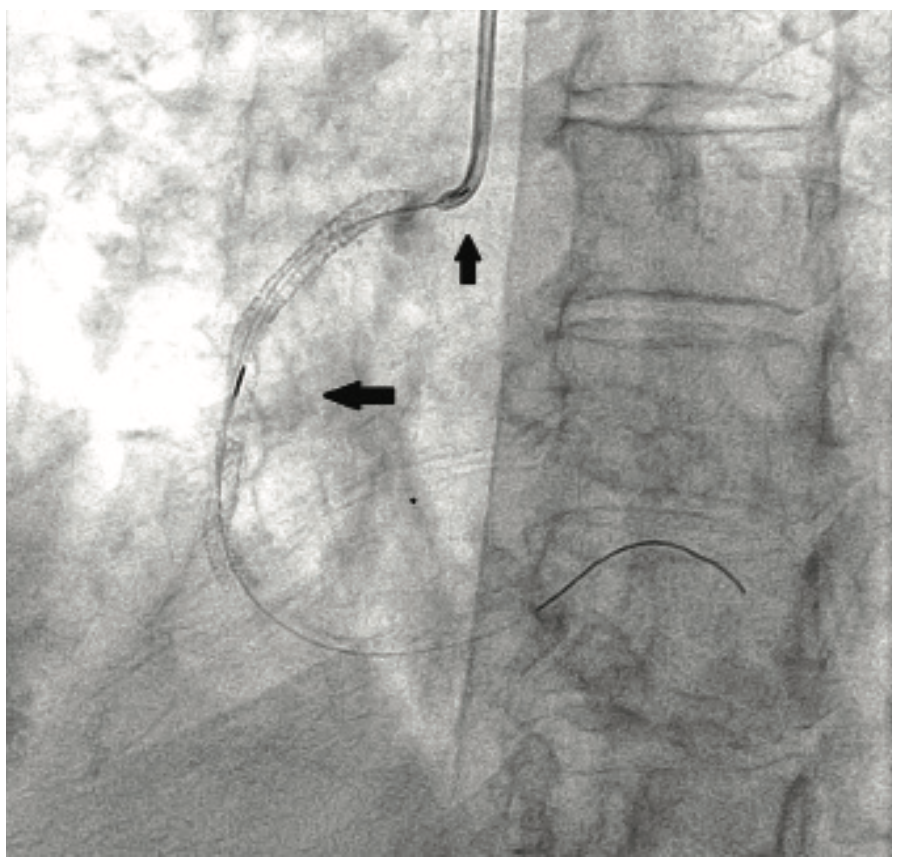

The patient’s prior procedures were performed via transfemoral approach and on one occasion, she experienced severe local pain due to vascular hemorrhage. The coronary brachytherapy procedure was performed using left radial artery access with a 6 Fr 10 cm long Slender Glidesheath (Terumo) and anticoagulation with bivalirudin. Baseline angiography showed sequential, high-grade restenotic lesions in the proximal right coronary artery (RCA) stents in addition to significant stenosis at the outflow of the most distal stent (Figure 2A). The in-stent restenosis was treated with laser atherectomy using an X-80 excimer catheter (Spectranetics) followed by balloon angioplasty with a 3.5 mm Angiosculpt scoring balloon (Spectranetics) and 4.0 mm NC Euphoria balloon (Medtronic). The most distal lesion, which extended beyond the prior stents, was treated with a new Promus DES. Coronary brachytherapy of the proximal lesions was then performed with a Beta-Cath 40 mm long source for a treatment dose of 23 Gray (Figure 2B). Final angiographic result is shown in Figure 2C. Repeat cardiac catherization at 3 months, performed because of chest pain, demonstrated widely patent stents. The patient has continued on aspirin and clopidogrel, and remains symptom-free 1 year post procedure.